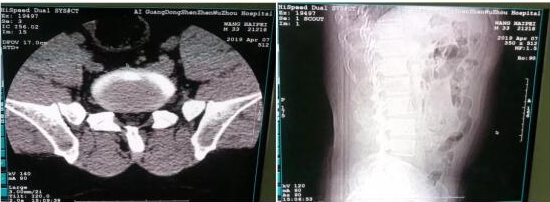

上图为王先生腰部CT拍片影像

第二天王先生坐着轮椅在家人的陪同下走进了深圳五洲医院,入院后经过CT检查被诊断为“腰椎间盘突出”。